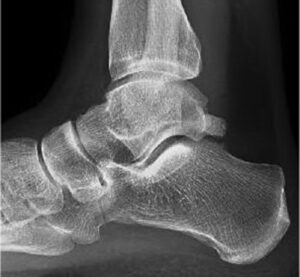

En la imagen mostramos una radiografía lateral en carga de un paciente con limitación a la flexión dorsal del tobillo. El paciente padece pinzamiento de tobillo, choque o impingement. Se produce debido a la colisión de las superficies óseas de astrágalo y tibia en la zona que señalamos.

Habitualmente los pacientes con esta patología refieren dolor cuando están caminando y cargando todo el peso en el pie. Este momento coincide con el 2º rocker del paso, cuando se debe producir un avance de la tibia sobre el astrágalo sin ningún tipo de limitación.